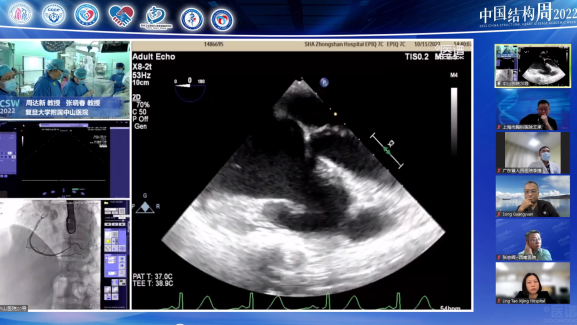

其他频道——聚焦PFO、三尖瓣病变

复旦大学附属中山医院周达新教授团队(团队成员包括潘文志教授、张晓春教授等),西安交通大学附属第一医院张玉顺教授团队,上海市肺科医院宫素岗教授团队和海军军医大学第一附属医院陆方林教授团队,就PFO(卵圆孔未闭)、CTEPH BPA(慢性血栓栓塞性肺动脉高压-经皮球囊肺血管成形术)和三尖瓣反流进行精彩手术转播。

本频道还进行了精彩的学术讲座,专家就PFO介入治疗导丝进入心包的处理,先心介入的器械发展史,房间隔缺损不全封堵的应对策略,以及肺静脉狭窄的介入诊疗进行精彩汇报。